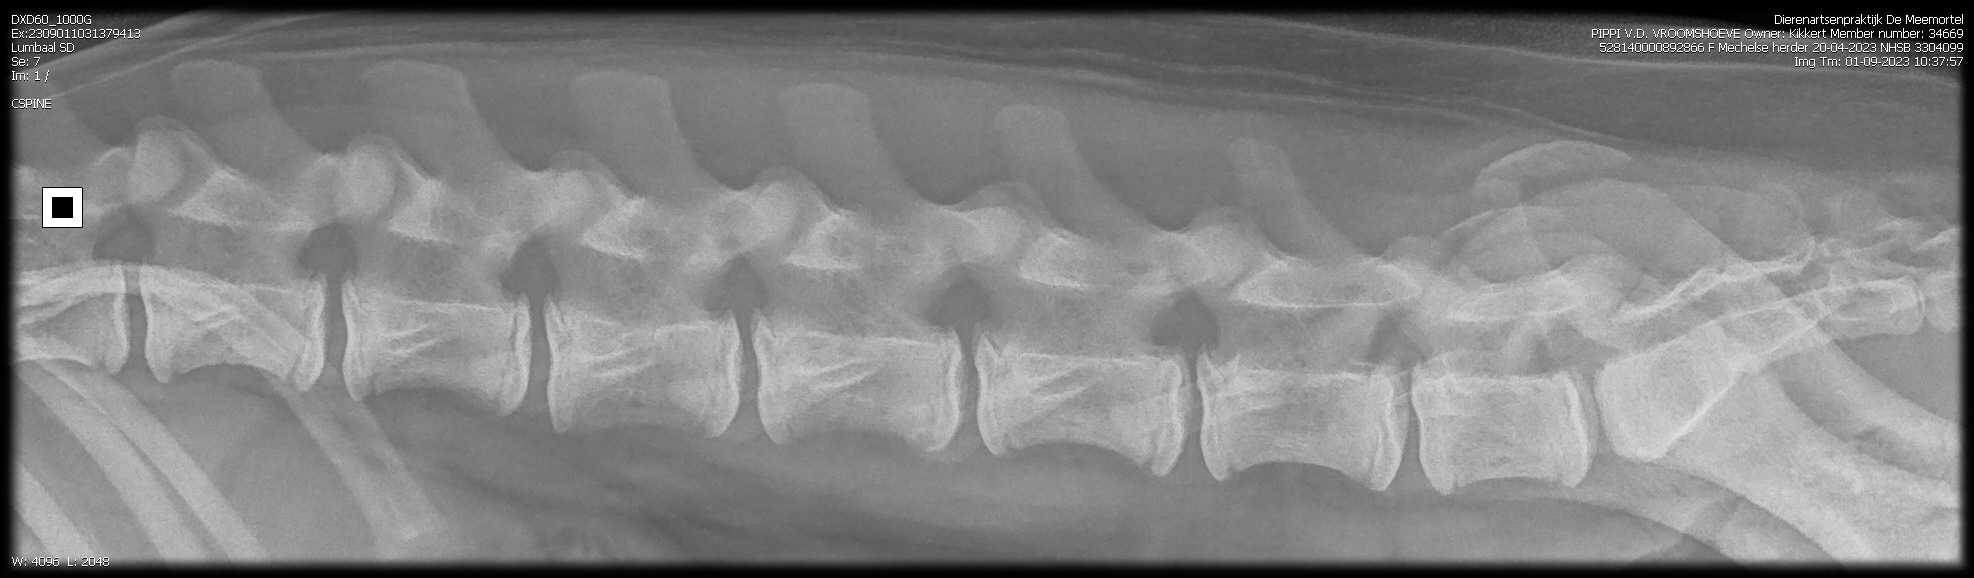

PennHip : Rechts DI 0.28 Links DI 0.16